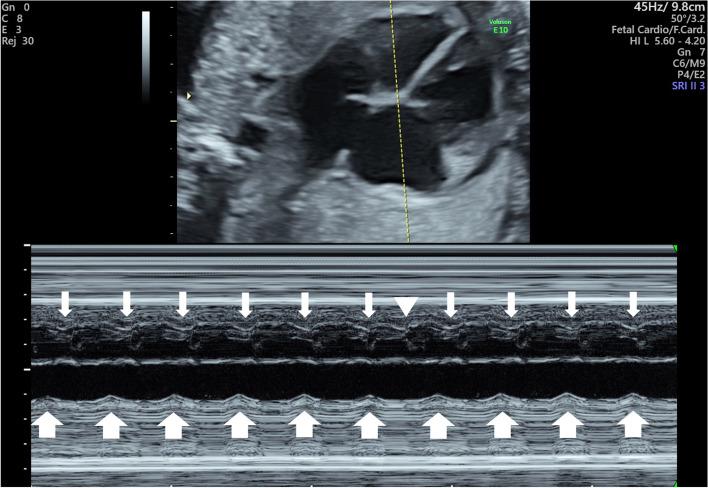

A 32-year-old, gravida 2, para 1, woman in whom fetal JET could not be diagnosed prenatally because the fetal heart rate was within the normal range. The fetus was diagnosed with premature restriction of the foramen ovale, and a cesarean section was performed, owing to the right heart overload that was characterized by fetal ascites and abnormal fetal Doppler velocity. Postnatally, the female neonate was diagnosed with JET on a 12-lead electrocardiogram, which revealed a neonatal heart rate of 158 bpm with narrow QRS and atrioventricular dissociation. After failure to respond to amiodarone therapy, she was treated with flecainide, which controlled the JET rate from 120 to 150 bpm. Fetal tachycardia with ventriculo-atrial (VA) dissociation or 1:1 VA conduction with a shorter VA interval than that of atrioventricular reentrant tachycardia confirmed the diagnosis of fetal JET.

一名 32 岁的孕妇,G2P1,因胎儿 JET 无法在产前诊断,因为胎儿心率在正常范围内。胎儿被诊断为卵圆孔过早限制,并因右心负荷过重而行剖宫产术,表现为胎儿腹水和胎儿多普勒速度异常。产后,女性新生儿在 12 导联心电图上被诊断为 JET,显示新生儿心率为 158bpm,QRS 波群窄,房室分离。在胺碘酮治疗无效后,她接受了氟卡尼治疗,将 JET 率从 120 到 150bpm 控制。胎儿心动过速伴室房(VA)分离或 1:1VA 传导,VA 间隔短于房室折返性心动过速,可确诊为胎儿 JET。